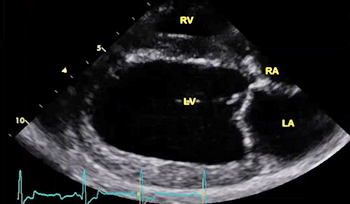

The echocardiograph examination shows the dimensions of the heart chambers, wall thickness and movement, valve movement and lesions, fractional shortening, among other characteristics. The echo screen shows the amount of wall contraction, which enables the operator to determine contractility, preload*, and afterload*. These factors are used to calculate "fractional shortening" (FS%) which is used as an indication of ventricular performance and of myocardial contractility.

* Preload is the blood filling the left ventricle, thereby stretching the heart muscle cells before contraction. Afterload is the blood contained in the left ventricle against which the heart contracts to eject that blood into the arteries.

See, also, this March 2017 article, in which the same investigators used 3-D echocardiography analysis on 113 dogs, including 13 cavaliers affected in varying stages of MVD. The 3-D echos enabled the investigators to compare the morphology of the mitral valves (MVs) of healthy dogs (none were CKCSs) and MVD-affected dogs. They report that the study demonstrated that the MVs of MVD-affected dogs differed from those of healthy dogs in several morphological aspects. In particular, the affected dogs had an increased sphericity and a decreased saddle shape of the MV annulus, as well as a decreased tenting height, area and volume. See Figure 1. The study also reportedly demonstrated significant differences in multiple 3-D echo MV measurements between dogs in varying stages (B1, B2, C) of MVD.

In an April 2021 article, Japanese cardiology researchers used three-dimensional transesophageal echocardiography (TEE) to examine 31 MVD-affected dogs, including 9 in Stage B2, 15 in Stage C, and 7 in Stage D. The TEE was performed while the dogs were under anesthesia prior to mitral valve repair surgeries. They found that the annulus height to commissural width ratio of Stage D dogs had significantly lower values than Stage B2 dogs, and that the aortic-mitral angle of Stages C and D dogs were significantly flatter than those in Stage B2. They concluded that the saddle shape of the mitral annulus and aortic-mitral angle were flatter in Stage D than those in the other two stages.

In an August 2021 study, Japanese cardiologists studied the shapes of the MVA in 59 healthy dogs and 371 MVD-affected dogs about to undergo mitral valve surgery. They reported finding that two-dimensional echocardiography revealed that the MVAs of the healthy dogs were elliptical and the annuluses of the MVD-affected dogs were larger than those of healthy dogs, and the annuluses remained rounder during the full cardiac cycle.